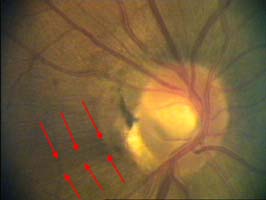

Na dolním pólu terče je patrný zálom vény, která zviditelňuje přítomnost i hloubku exkavace až k dolnímu okraji terče.